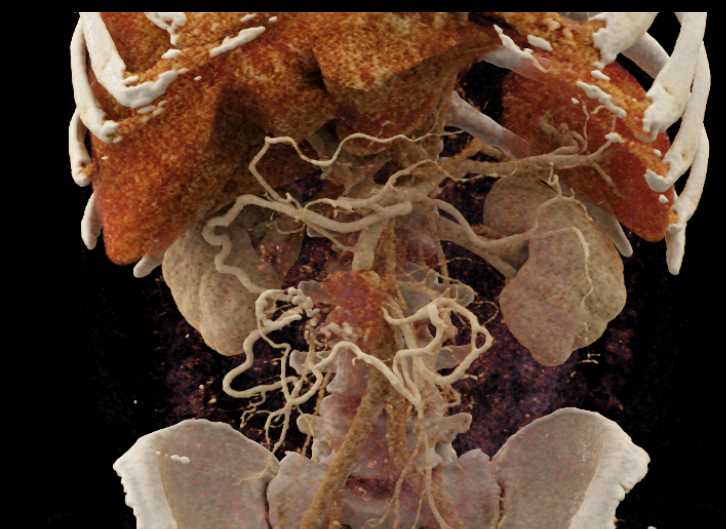

Carcinoid Tumor with Desmoplastic Reaction